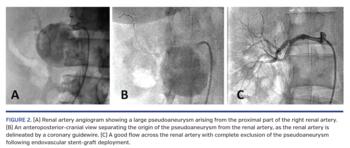

Selective right renal arteriogram following cannulation with Judkins Right 4, 6 Fr guide catheter revealed a large pseudoaneurysm arising from the proximal part of the renal artery, with a poor distal arterial run-off (Figure 2A; Video 1). A choicePT wire (Boston Scientific) could cross through the renal artery (Figure 2B). As an appropriately sized stent-graft was not available on shelf, a 4 x 16 mm GraftMaster PTFE coronary stent-graft (Abbott Vascular) was deployed to exclude the pseudoaneurysm. An additional 6 x 19 mm Omnilink Elite Renal bare-metal stent (Abbott Vascular) was deployed, covering the previously deployed under-sized stent-graft to optimize the end results. There was good flow across the renal artery with total exclusion of the pseudoaneurysm (Figure 2C; Video 2).